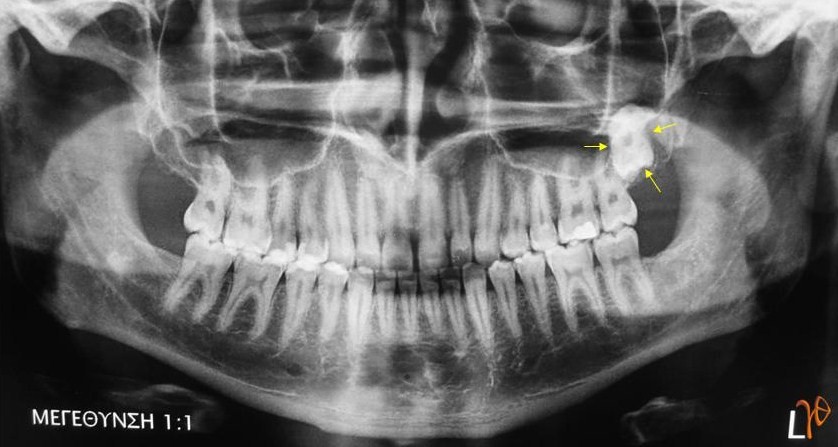

27-χρονος άνδρας με ελεύθερο ιατρικό ιστορικό, προσήλθε αναφέροντας πόνο κατά την κατάποση τους τελευταίους τρεις μήνες. Η κλινική εξέταση της στοματικής κοιλότητας και η πανοραμική ακτινογραφία δεν ήταν ενδεικτικές για βλάβες που να συσχετίζονται με τα συμπτώματα του ασθενή. Επίσης η παθολογική και ΩΡΛ εξέταση, μετά από υπερηχογράφημα τραχήλου και ενδοσκοπήσεις της ανωτέρας αεροπεπτικής οδού δεν κατέληξαν σε ύποπτα παθολογικά ευρήματα. Προτάθηκε ότι η παρουσία του άνω αριστερού εγκλείστου φρονιμίτη, ο οποίος απεικονιζόταν στην πανοραμική ακτινογραφία (Εικόνα 1), μπορεί να συσχετίζεται με την οδυνοφαγία παρά την απουσία φλεγμονής.

Εικόνα 1. Πανοραμική ακτινογραφία στην οποία απεικονίζεται ο άνω έγκλειστος φρονιμίτης (βέλη).